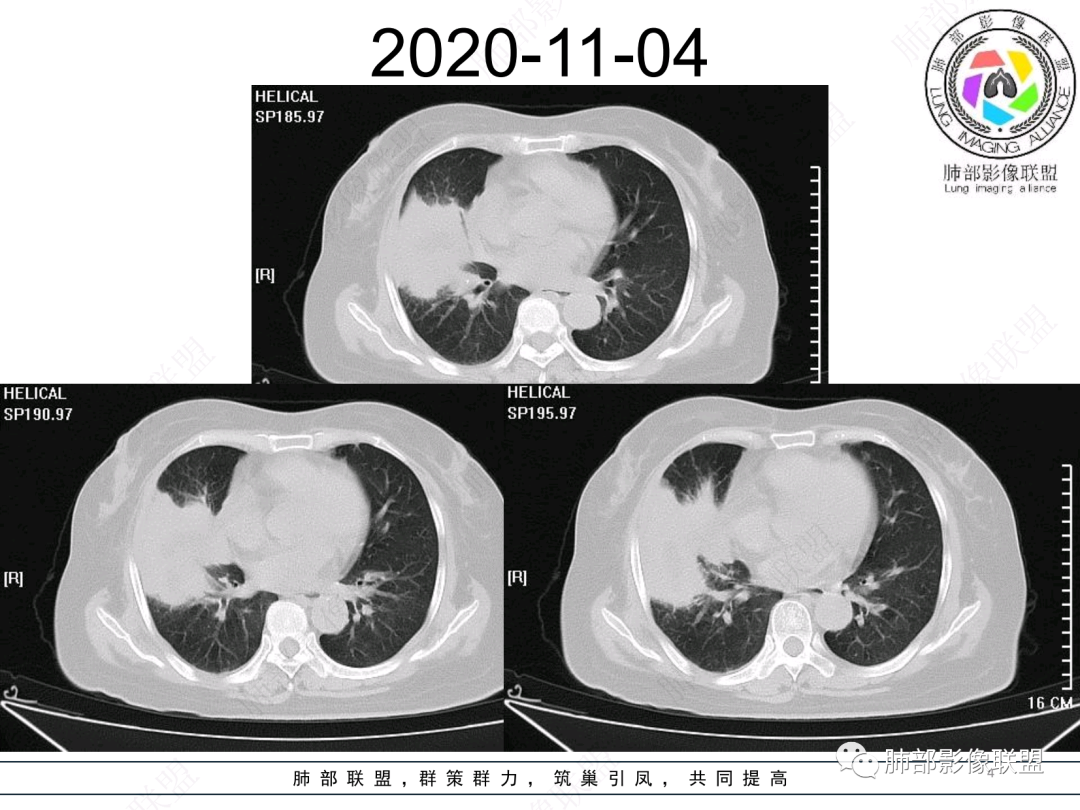

慢性咳嗽,抗炎复查无好转,原右肺中叶实边,外侧段支气管开口阻断,复查无好转,逐渐向下叶外前基底段融合形成大肿块,边缘膨隆,密度不均匀,坏死轮廓不清,内血管束破坏,累及中轴间质厚,外围分布,方向恶性,与炎性肉芽肿鉴别,隐球荚膜抗原先排查!

右肺中叶实变,支气管开口阻断,边缘膨隆,密度不均匀,坏死边界清晰,胸膜累及,。一般抗感染治疗无效。考虑恶性。

右肺中叶大片实变,内见大片的坏死,中叶外侧段支气管阻塞,相邻胸膜增厚,间隔约四个月后复查,发现低密度坏死内可见气泡影,老年人,反复迁延不愈的病变要考虑恶性,首先考虑腺癌伴感染。鉴别慢性脓肿。

老年女性,慢性病史,炎性指标稍高,肿标正常,右中下肺大片实变,跨叶生长,边界清,收缩力差,膨隆生长为主,支气管杵状截断,均匀强化,其内坏死边界清,可见悬浮气泡,整体观察,病灶膨隆生长为主,邻近肺野无播散灶,形态单一,尽管慢性病史,影像不支持OP和TB,支气管截断呈杵状,肿标正常,均匀强化,虽是高龄患者,诊断恶性肿瘤有点牵强,综和分析,首选炎性病变放线菌感染,其次考虑低度恶性占位炎机母。

这个病例,看长轴、形态,首先跨叶,里面的坏死腔,它是相通的,就是跨中叶及前基底段。

然后中叶与下叶的坏死腔病灶是相通的,病灶是跨叶的,胸膜糊墙为主。

我要看一下下叶。还想重建一下,就是按照我自己理解的长轴去重建出这个病灶的整体形态,我当时一看,好像侧向融合的病灶。侧向融合的病灶考虑慢性炎性病变的,有几种,这样大片的病灶,常规都考虑特殊感染多一些,比如隐球,放线菌,奴卡等,都可以这样的改变。